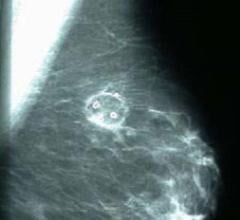

Despite decades of progress in breast imaging, one challenge continues to test even the most skilled radiologists ...